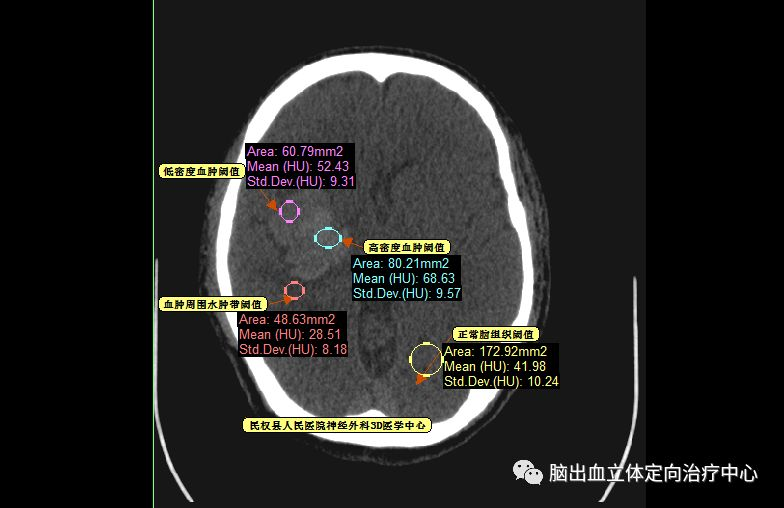

再仔细观察并划定血肿分层区域,可设定血肿为高密度区域、低密度区域,和正常脑组织对比

以红色区域划分为高密度区域、蓝色区域划分为低密度区域

测量各密度区域CT阈值,可见高密度区域(红色区域)CT阈值为60.66,低密度区域(蓝色区域)CT阈值为44.39,正常脑组织区域CT阈值为20.94。

可见血肿呈分层现象,血肿周围水肿带明显,利用3D测量其各相关CT阈值。